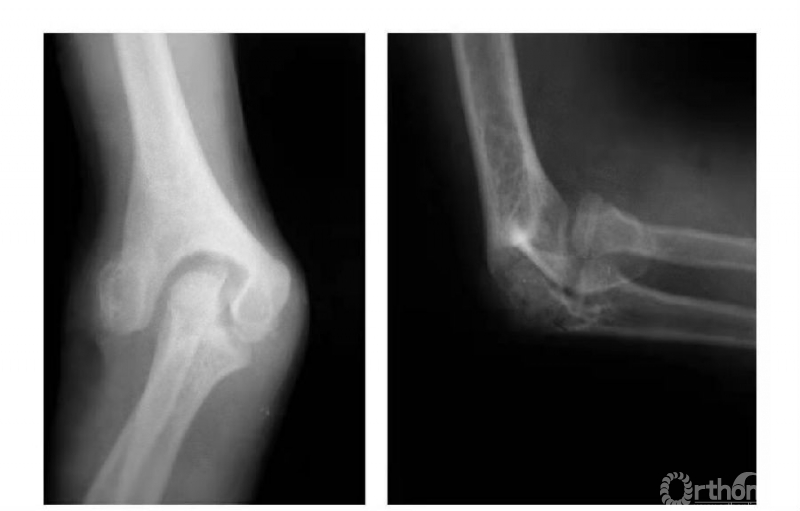

例3:肱骨内髁长斜形劈裂骨折(折线长约10cm)(图3)。

图3

例5:肱骨内髁外侧壁骨骺因损伤而早闭,而内外侧骨骺继续生长致滑车沟变深,继而肱骨下端形成鱼尾状畸形(图8)。

图8